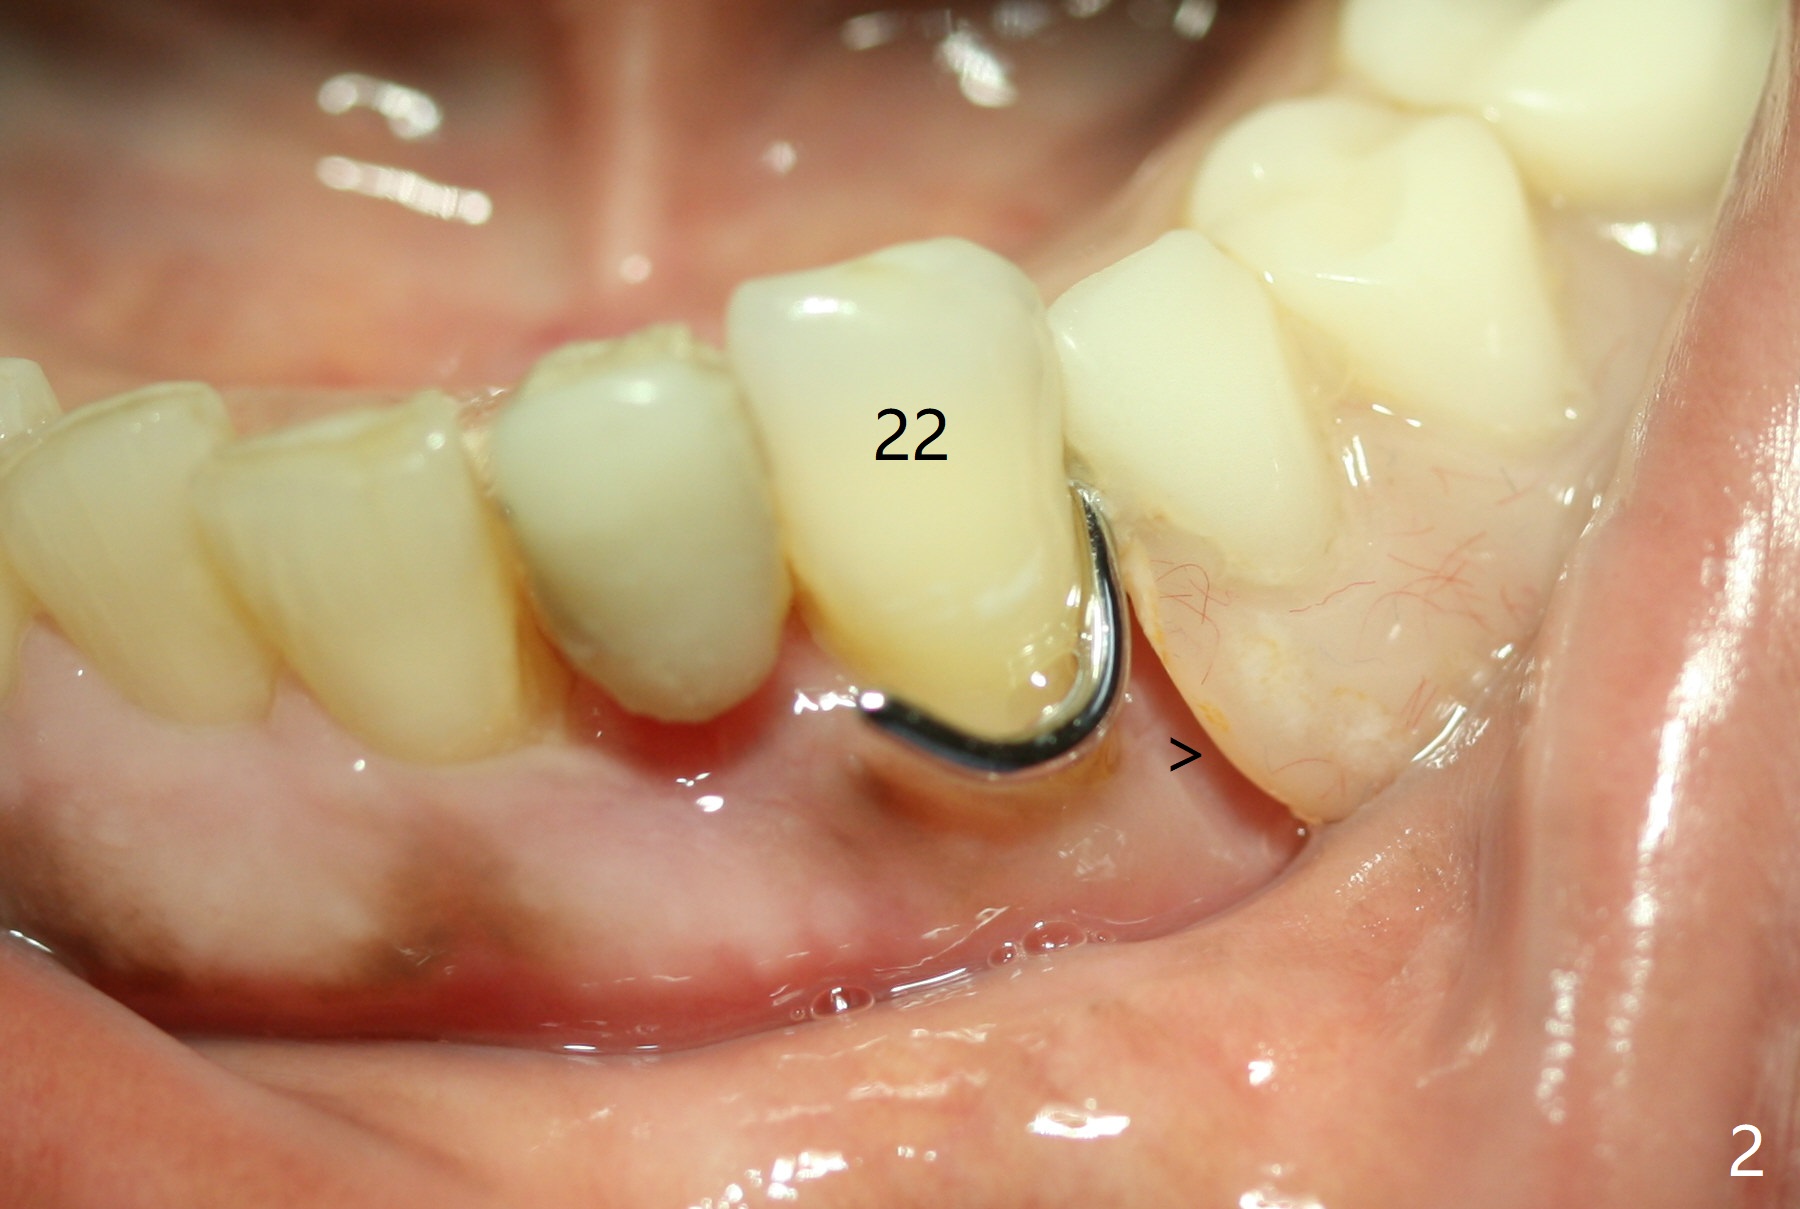

The inflammation around the tooth #22 (Fig.1 *) and mobility may be related to trauma from the only clasp of the lower flipper (Fig.2). The latter is loose with space underneath (>) and laterally (Fig.3 *). The distobuccal plate is defective upon extraction; the osteotomy is initiated in the mesiolingual slope of the socket (Fig.4) with ~ 6 mm native bone. When a 3.8x15 mm dummy implant achieves insertion torque of 50 Ncm, the insertion is incomplete with apical space (Fig.5 *). The definitive implant (3.8x13 mm) closes the apical space and obtains insertion torque >55 Ncm; a ball abutment with 2 mm cuff seems to be short for retention (Fig.6). A 4.5x4(5) mm cemented abutment (Fig.7,8) seems appropriate for retention after soft reline of the lower flipper (Fig.9-11). The socket heals without bone graft exposure 8 days postop (Fig.12,13). To satisfy the patient's desire to have a white tooth, the buccal portion of the soft reline and the abutment is removed (Fig.14) and a crown form is added (Fig.15 *). The socket obliterates 3 months postop (Fig.16).